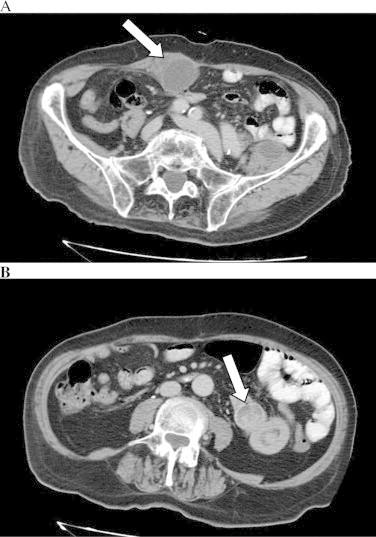

PRESENTATION OF CASE

An 87-year-old man treated 3 years previously for colonic adenocarcinoma with left colectomy, was brought to our attention with a 4.5cm×3.5cm mass in the proximal jejunum associated with another abdominal wall enhancing mass of 5cm in diameter in the rectus muscle. Diagnosis on gross examination after surgical resection was adenocarcinoma stage III (T4N1M0) with involvement of lymph nodes.

一名87岁男性,3年前因结肠腺癌接受左半结肠切除术,现因空肠近端有一个4.5cm×3.5cm的肿块以及腹直肌处另一个直径5cm的腹壁强化肿块而引起我们的注意。手术切除后大体检查诊断为III期腺癌(T4N1M0),伴有淋巴结受累。